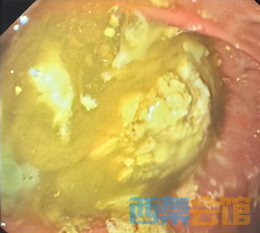

也就是说,导致林先生昏迷不醒的——正是胃里还在持续释放毒性的药团,再叠加吸入性肺炎。 如果不能尽快清除药团,多器官功能衰竭、死亡将接踵而至。 藏在胃里的**库 常规洗胃根本清不掉 “很多人都以为,药物中毒只要洗胃就万事大吉,这是个误区。”北京大学深圳医院急诊科副主任杨莹解释道。 一次性吞服超过50片片剂,尤其是缓释、控释剂型的药物,在胃酸、胃粘液的共同作用下,极易相互粘结,形成质地坚硬的药石。 而林先生混着白酒吞服的行为,更是雪上加霜: 酒精不仅会加速药物吸收,让中枢抑制的效果翻倍,中毒症状来得更快更猛,还会抑制胃的蠕动,延缓药物排出,给药石的形成创造了完美的条件。 等到中毒快反团队介入时,林先生胃里的药石已经基本成型。 常规洗胃管的孔径有限,只能抽出粉末状、小颗粒的药物残留,对于这种凝结成块的药团根本无法触及。 而这颗留在胃里的药石,就像一个埋在胃里的“缓释毒库”,会持续不断地向胃肠道释放药物,被人体吸收入血,导致患者血药浓度居高不下,中毒症状持续加重,甚至突然恶化。 呼吸抑制、多器官损伤、心跳骤停的风险都在飙升。 50次反复冲洗 43分钟清空致命药团 中毒快反团队最终敲定了救治方案:胃镜下取“药石”,从根源上掐断毒物的释放。林先生被立即转入EICU,全麻下行气管插管保护气道。 内镜顺着食道缓缓送入,镜头里的画面让所有人都心头一紧:食管管腔里遍布黄色药渣残留,胃底更是被一大团质软易碎的黄色团块堵得严严实实,那正是150余片药凝结成的“药石”。

这场清洗持续了43分钟,直到内镜下再也看不到明显的药渣残留:食管、胃底、胃体、十二指肠里的药物被彻底清除干净,这场惊心动魄的拆毒团行动,终于宣告成功。 术后第二天,林先生的神志彻底清醒,